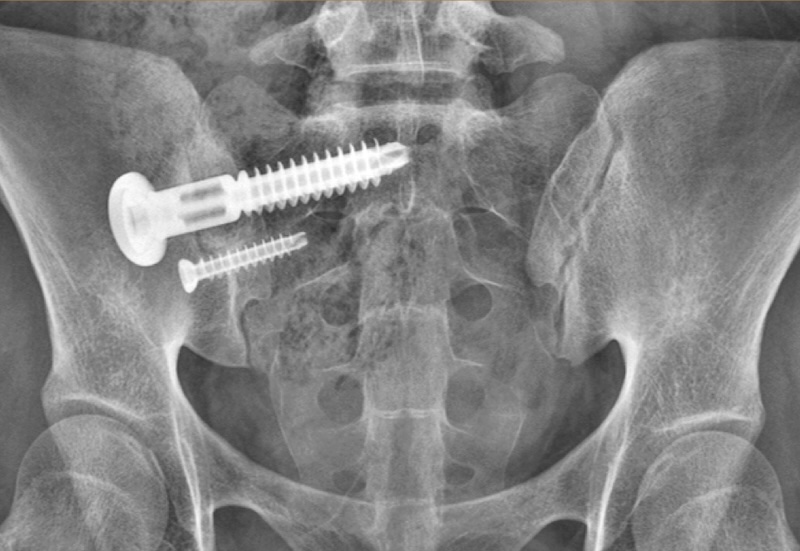

Integrity-SI Fusion System Sacro-Iliac Screw

MANUFACTURER INFO:Integrity-SI Fusion System

The Integrity-SI Sacro-iliac fusion system by OSteoCentric is a minimally invasive lateral SI joint stabilization. It features an etched titanium lag bolt with a large compression washer to provide compression across the SI joint. The Integrity-SI features a large window that spans the SI joint to facilitate bone graft and bony ingrowth. The surface treatment of the screw allows increased bony purchase for osseointegration. The system feautres a proprietary BladeX instrument that facilitates cleaning out and decortication of the SI joint

• Titanium with etched surface treatment to increase osseointegration

• Large graft window to span the SI joint

• Large compression washer to squeeze SI joint together to facilitate fusion

• Optional secondary anti-rotation screw